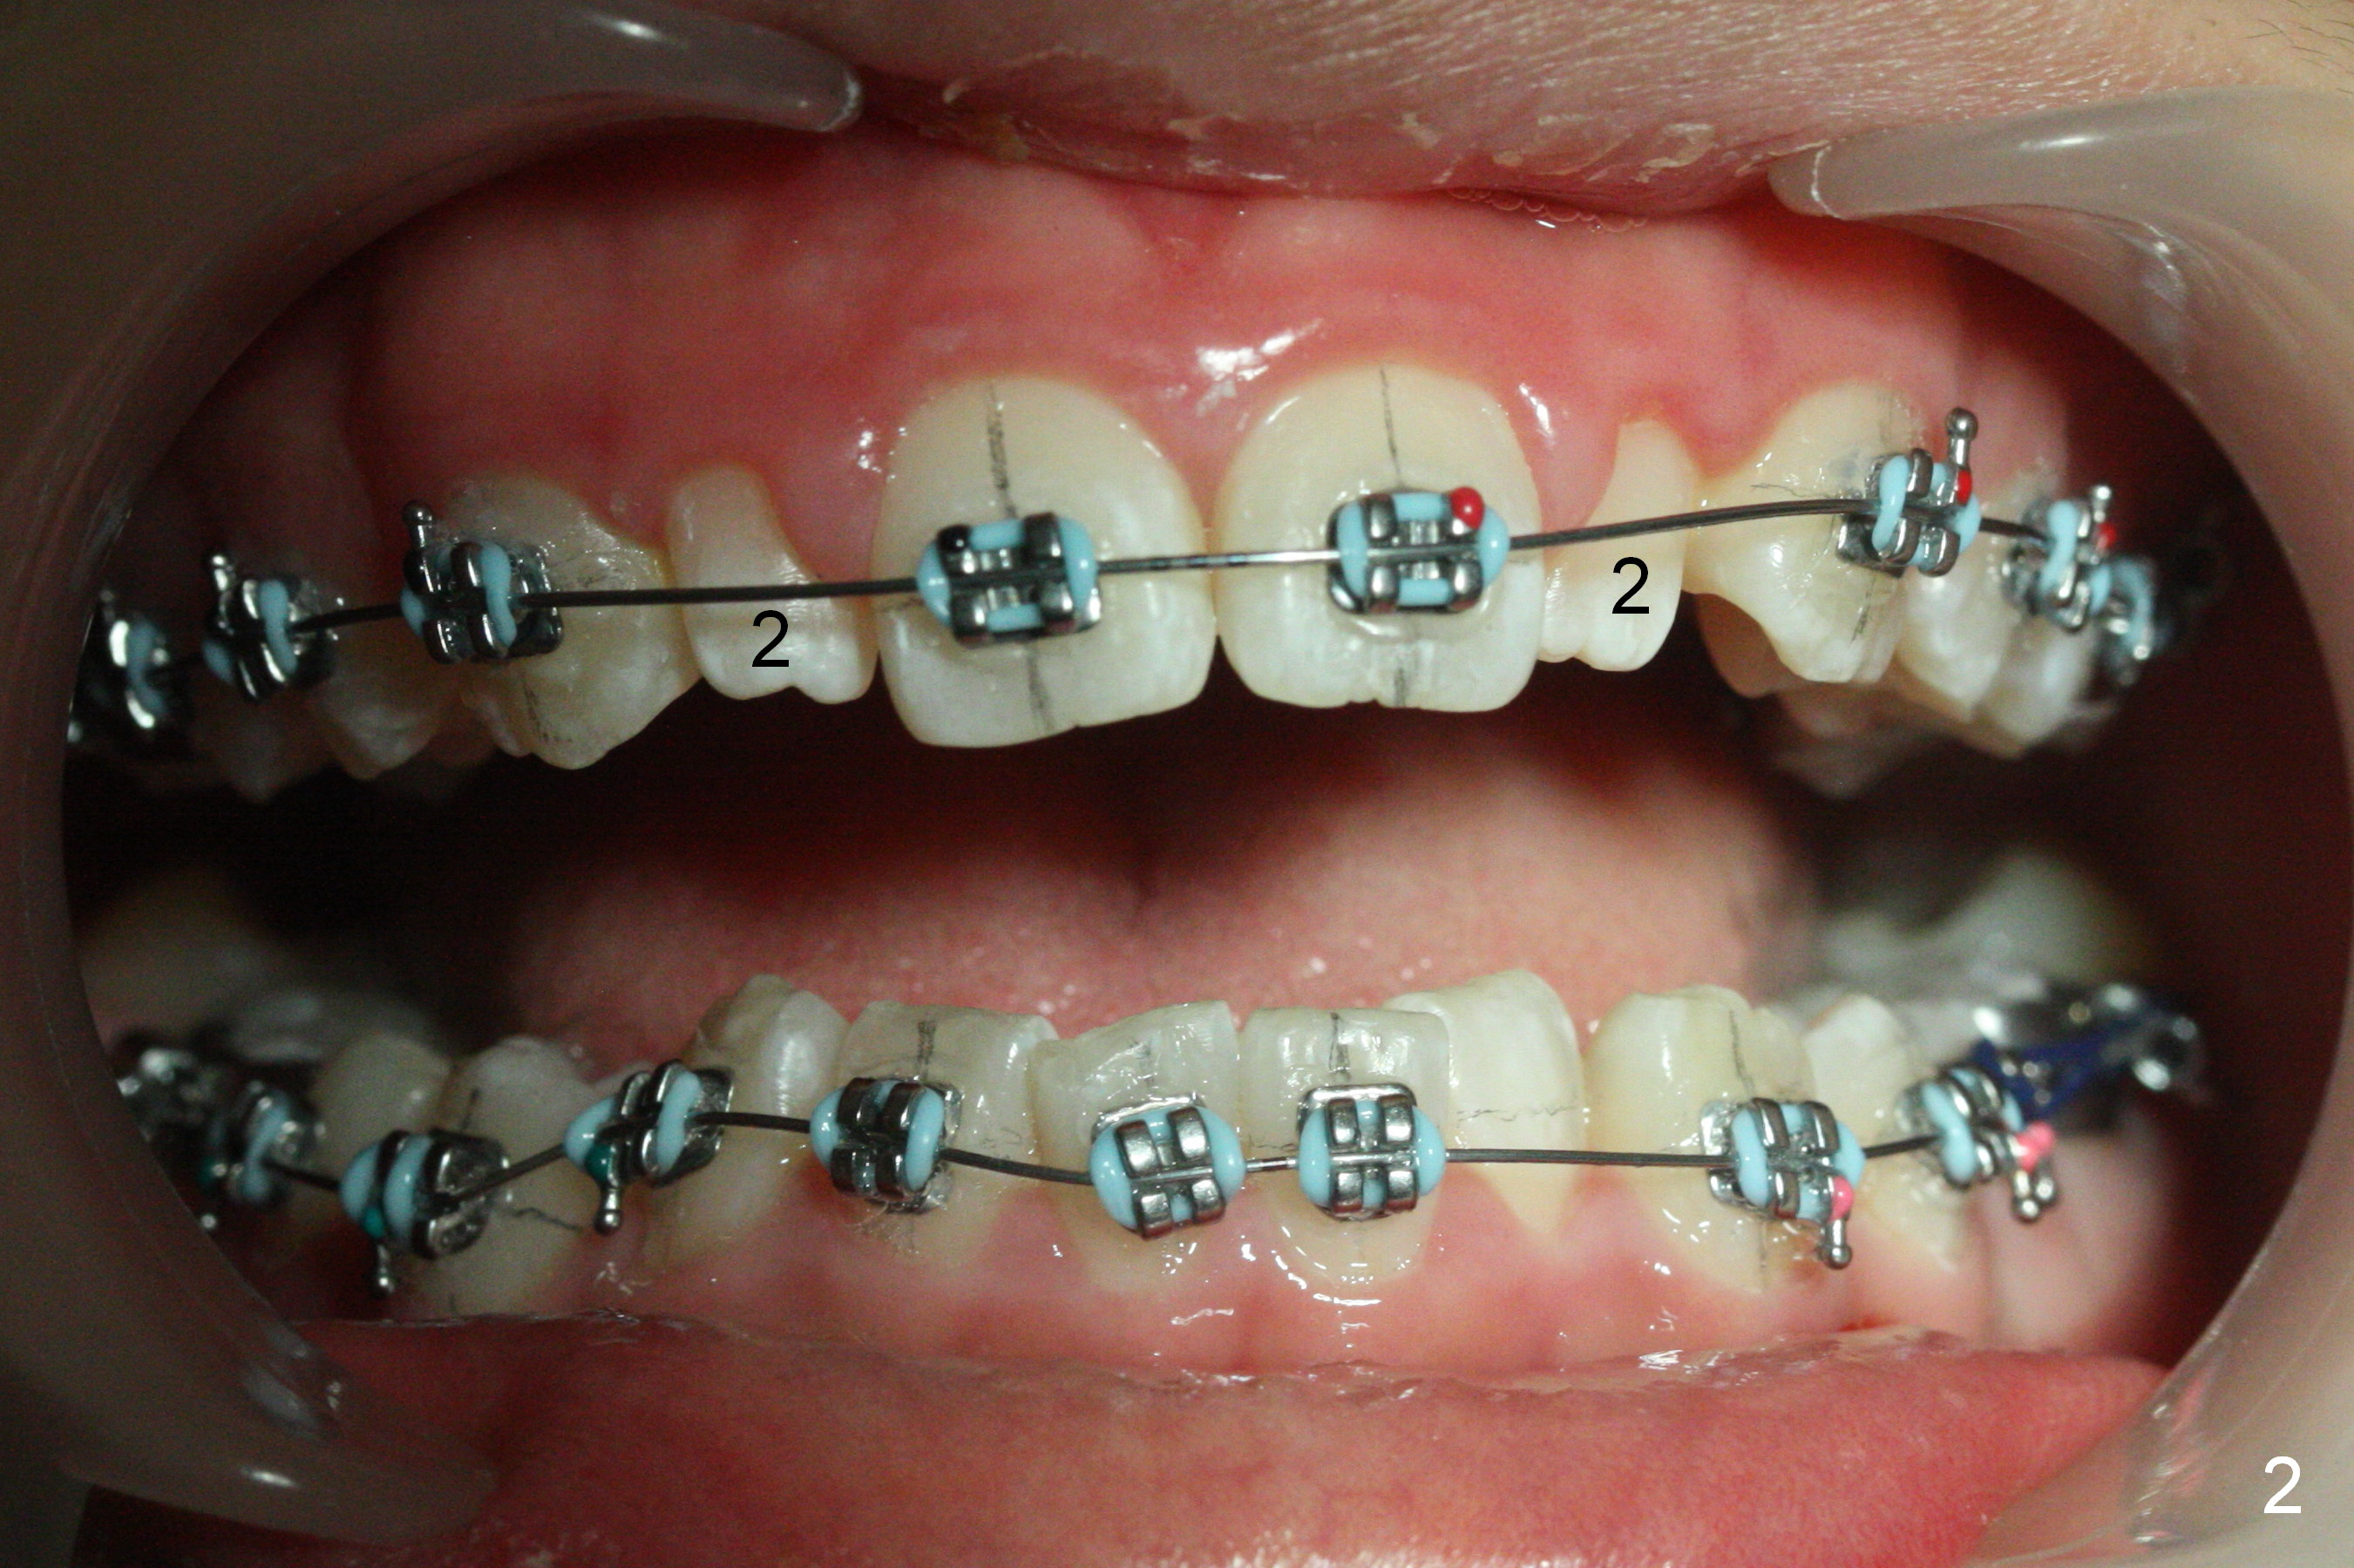

As planned, the peg laterals do not have brackets placed (Fig.2), since their position and shape will be ultimately decided by veneers. Alignment of the lower arch is more severe than that of the upper one, characterized by severe crowding at LR 3 and 4 (Fig.1) and rotation of LL 5 (Fig.3). Oral hygiene does not improve during orthodontic treatment. Impression will be taken prior to debanding. Space is obtained for LL2; brackets are placed at LL2 and 5; 14 niti wire is placed 9 months post banding (Fig.4-6). Orthodontic treatment is terminated prematurely partially due to poor oral hygiene.